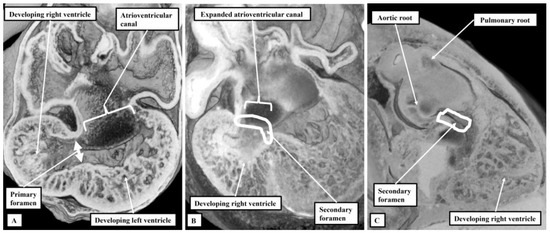

3.1. Evidence from Development